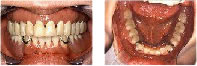

インプラント埋入後の状態です。

インプラントが安定したら上部構造(歯)をつくり噛める状態になり、見た目の問題も解消されました。